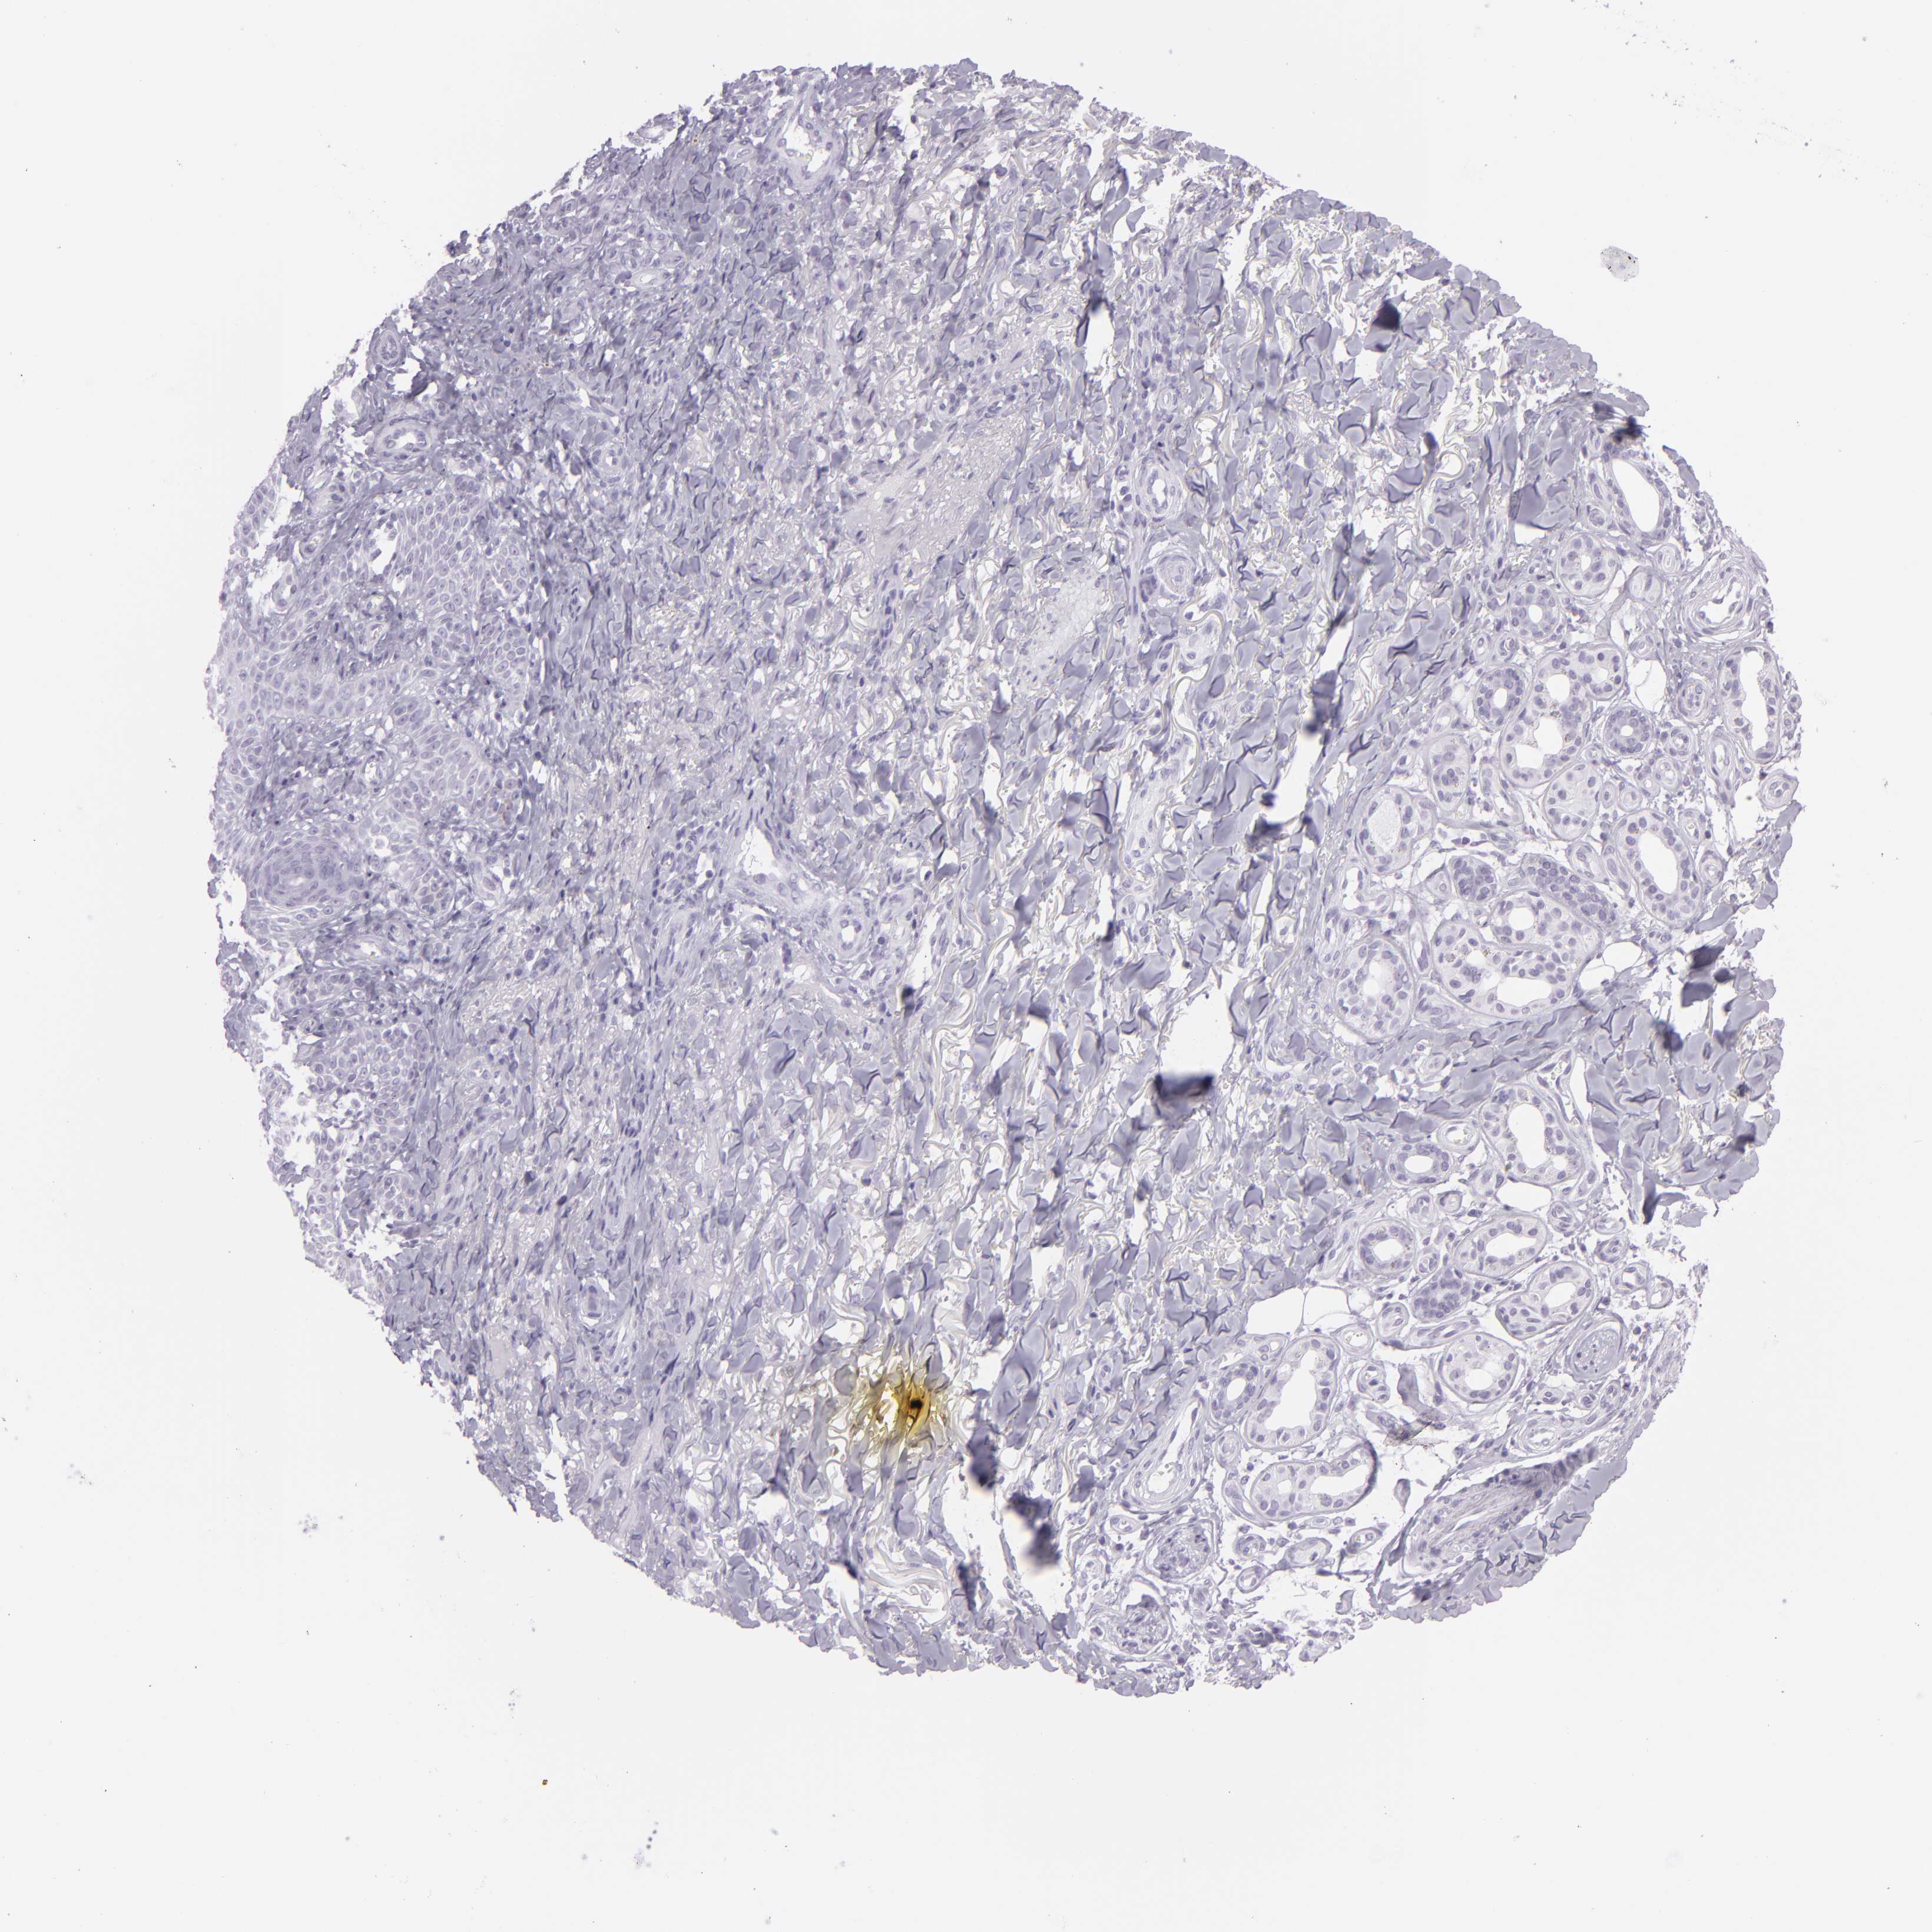

SKIN CANCER - Protein expressioni

A mouse-over function shows sample information and annotation data. Click on an image to view it in a full screen mode. Samples can be filtered based on level of antibody staining by selecting one or several of the following categories: high, medium, low and not detected. The assay and annotation is described here.

Antibody stainingi

Antibody staining in the annotated cell types in the current human tissue is reported as not detected, low, medium, or high, based on conventional immunohistochemistry profiling in selected tissues. This score is based on the combination of the staining intensity and fraction of stained cells.

Each image is clickable and will lead to virtual microscopy that enables deeper exploration of all samples and also displays staining intensity scores, fraction scores and subcellular localization as well as patient and tissue information for each sample.

Antibody CAB002165

Squamous cell carcinoma, NOS